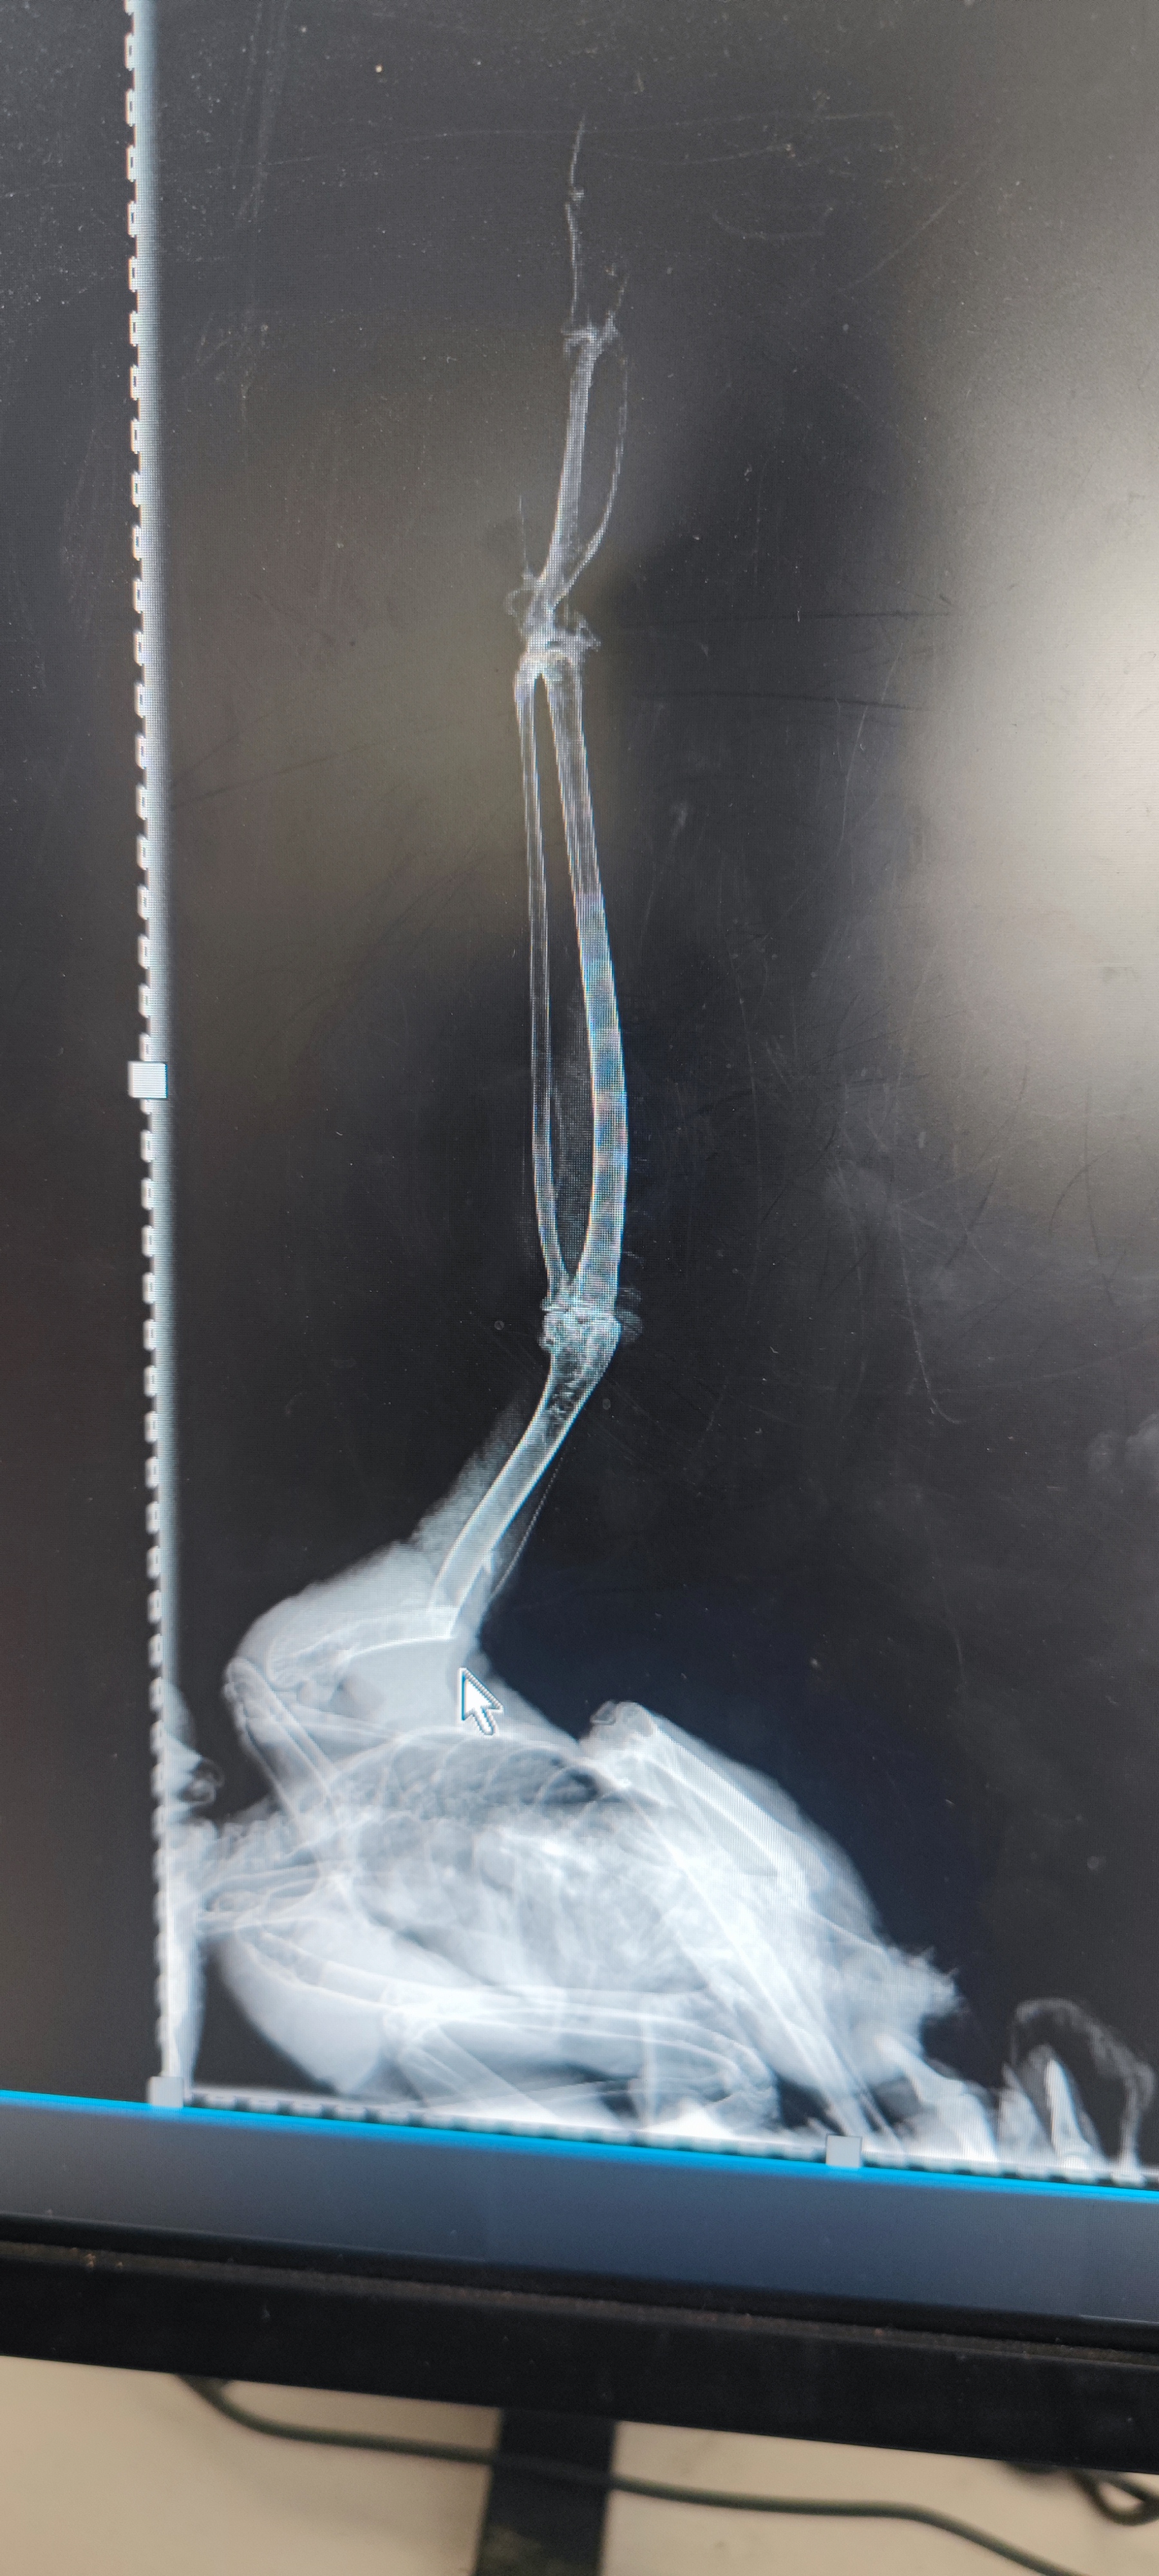

►中心为被弹弓打断翅膀的猛禽:游隼进行清创,并实行接骨手术